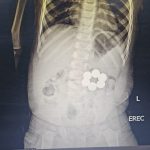

بدأت تفاصيل الحالة عند استقبال مستشفى الأطفال للطفل، وهو يعاني من أعراضٍ مقلقةٍ استدعت التدخل الطبي الفوري؛ حيث كشفت الفحوصات والأشعة التشخيصية عن وجود ستِّ قطعٍ مغناطيسيةٍ داخل الجهاز الهضمي.

وتحمل هذه الحالة احتماليةَ التصاق القطع المغناطيسية بجدران الأمعاء، وهو ما قد يؤدي إلى حدوث ثقوبٍ أو انسدادٍ معويٍّ أو مضاعفاتٍ خطيرةٍ حالَ عدم التدخل العاجل.

ونجح الفريق الطبي في استخراج جميع القطع المغناطيسية باستخدام المنظار بدقةٍ عاليةٍ خلال فترةٍ زمنيةٍ وجيزة، دون تسجيل أيِّ مضاعفاتٍ أثناء الإجراء أو بعده، مع الحفاظ الكامل على سلامة الجهاز الهضمي؛ ليخرج الطفل في حالةٍ مستقرةٍ إكلينيكيّّا، ويغادر المستشفى بصحةٍ جيدة.